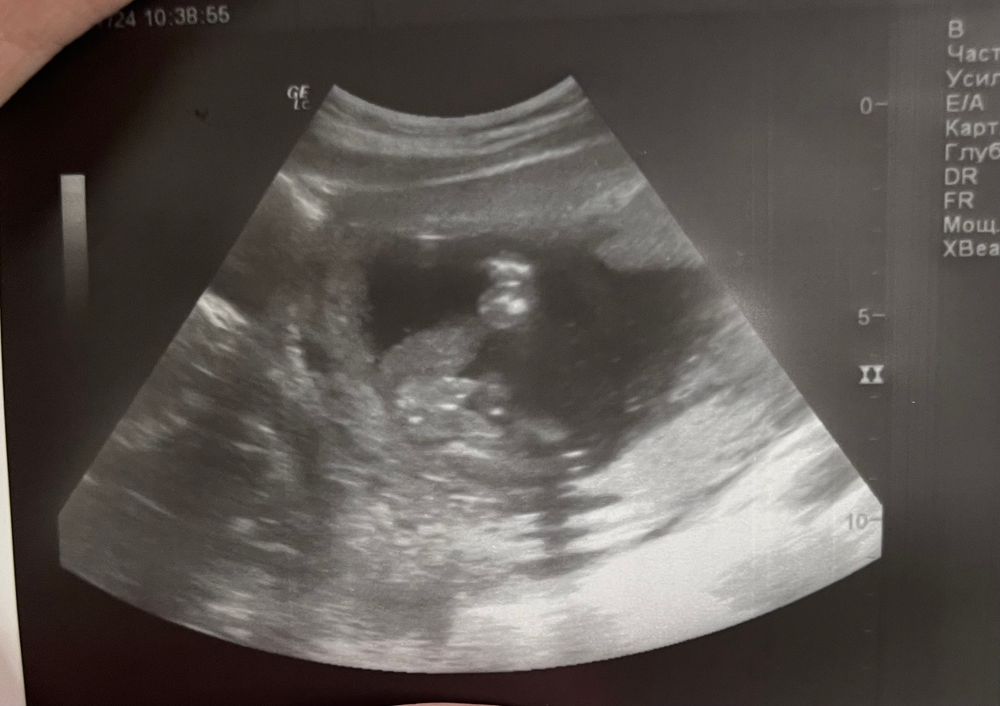

Пол в 16 недель

Мальчик) он словно ручкой за писюн тянет 😅

Мне кажется там бубенчики🤭

Бубенчики торчат,мальчик 😁😁

Какая же это пуповина? Мальчик это

Мальчик 100% Узист лукавит зачем-то 🙄

Пол малыша по фото УЗИ. Мамы мальчиков, поделитесь опытом